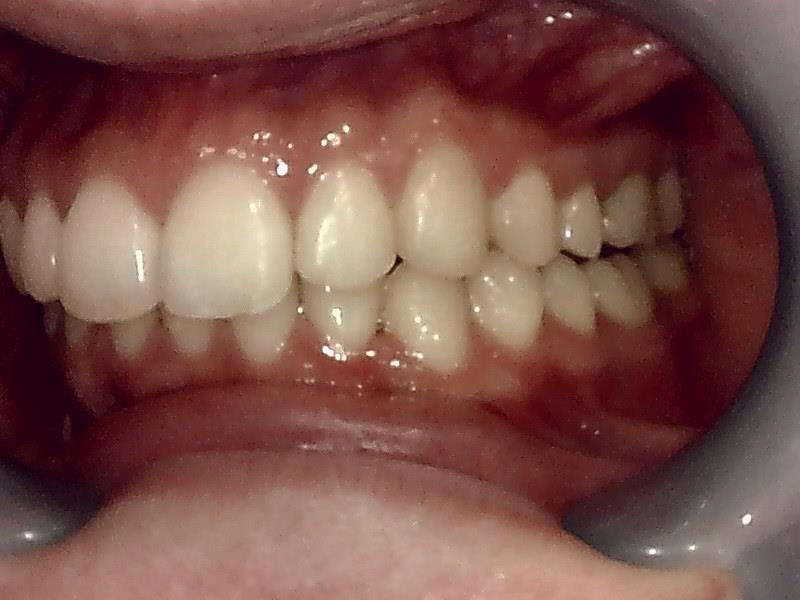

左側